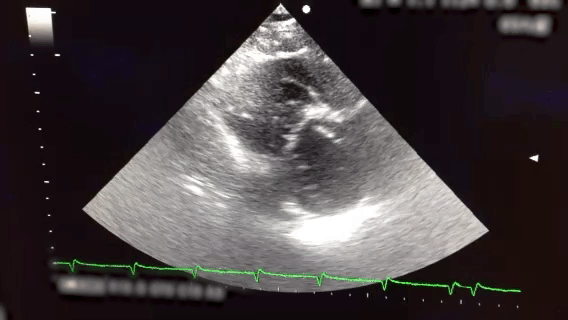

A Patient with Pulmonary Embolism Treated with Systemic Thrombolysis 圖一 Four chamber view-v1 圖一 Parasternal short axis view (已後製 裁切消音)-v1 圖三 Four chamber view (已後製 裁切消音)-v1 圖三 Parasternal short axis view (已後製 裁切消音)-v1 返回 VTE Casebook